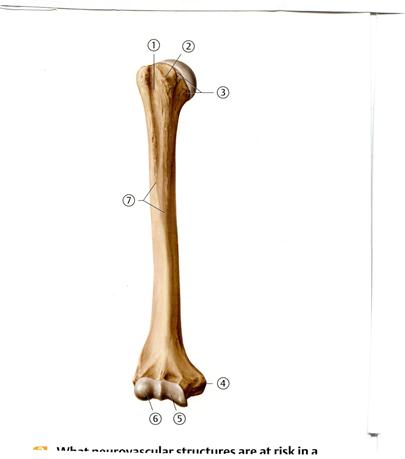

Е. Үлкен бөксе

42. Төменде көрсетілген суреттегі белгіленген №5 анатомиялық құрылымды атаңыз.

+С. Жоғарғы буын беті